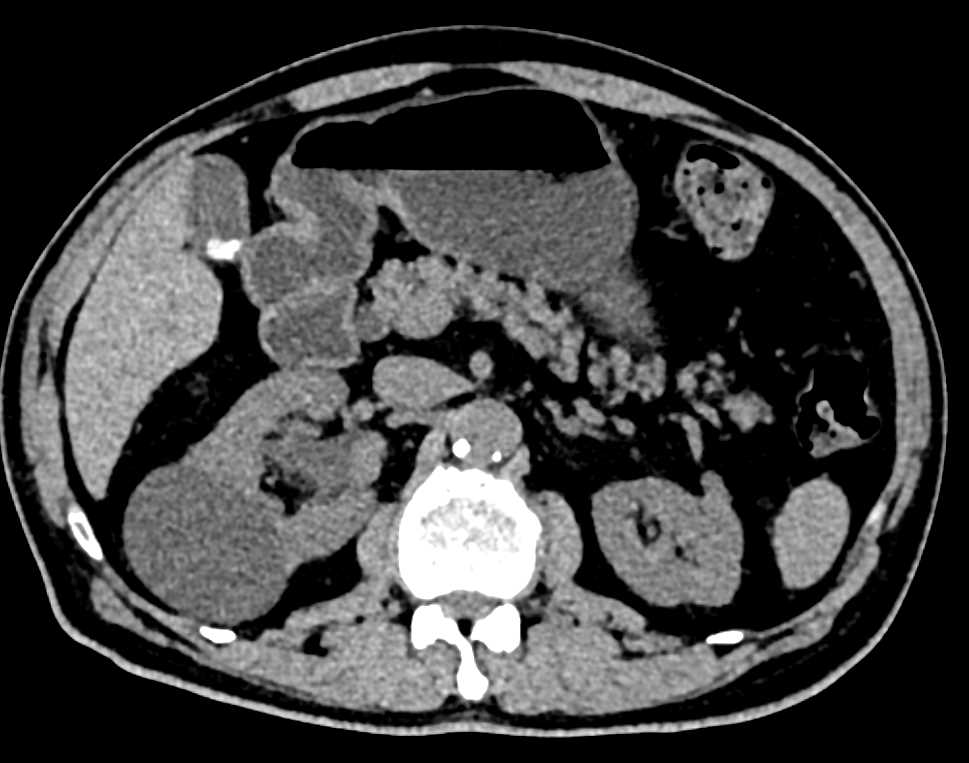

Transitional Cell Carcinoma Right Kidney and Bladder